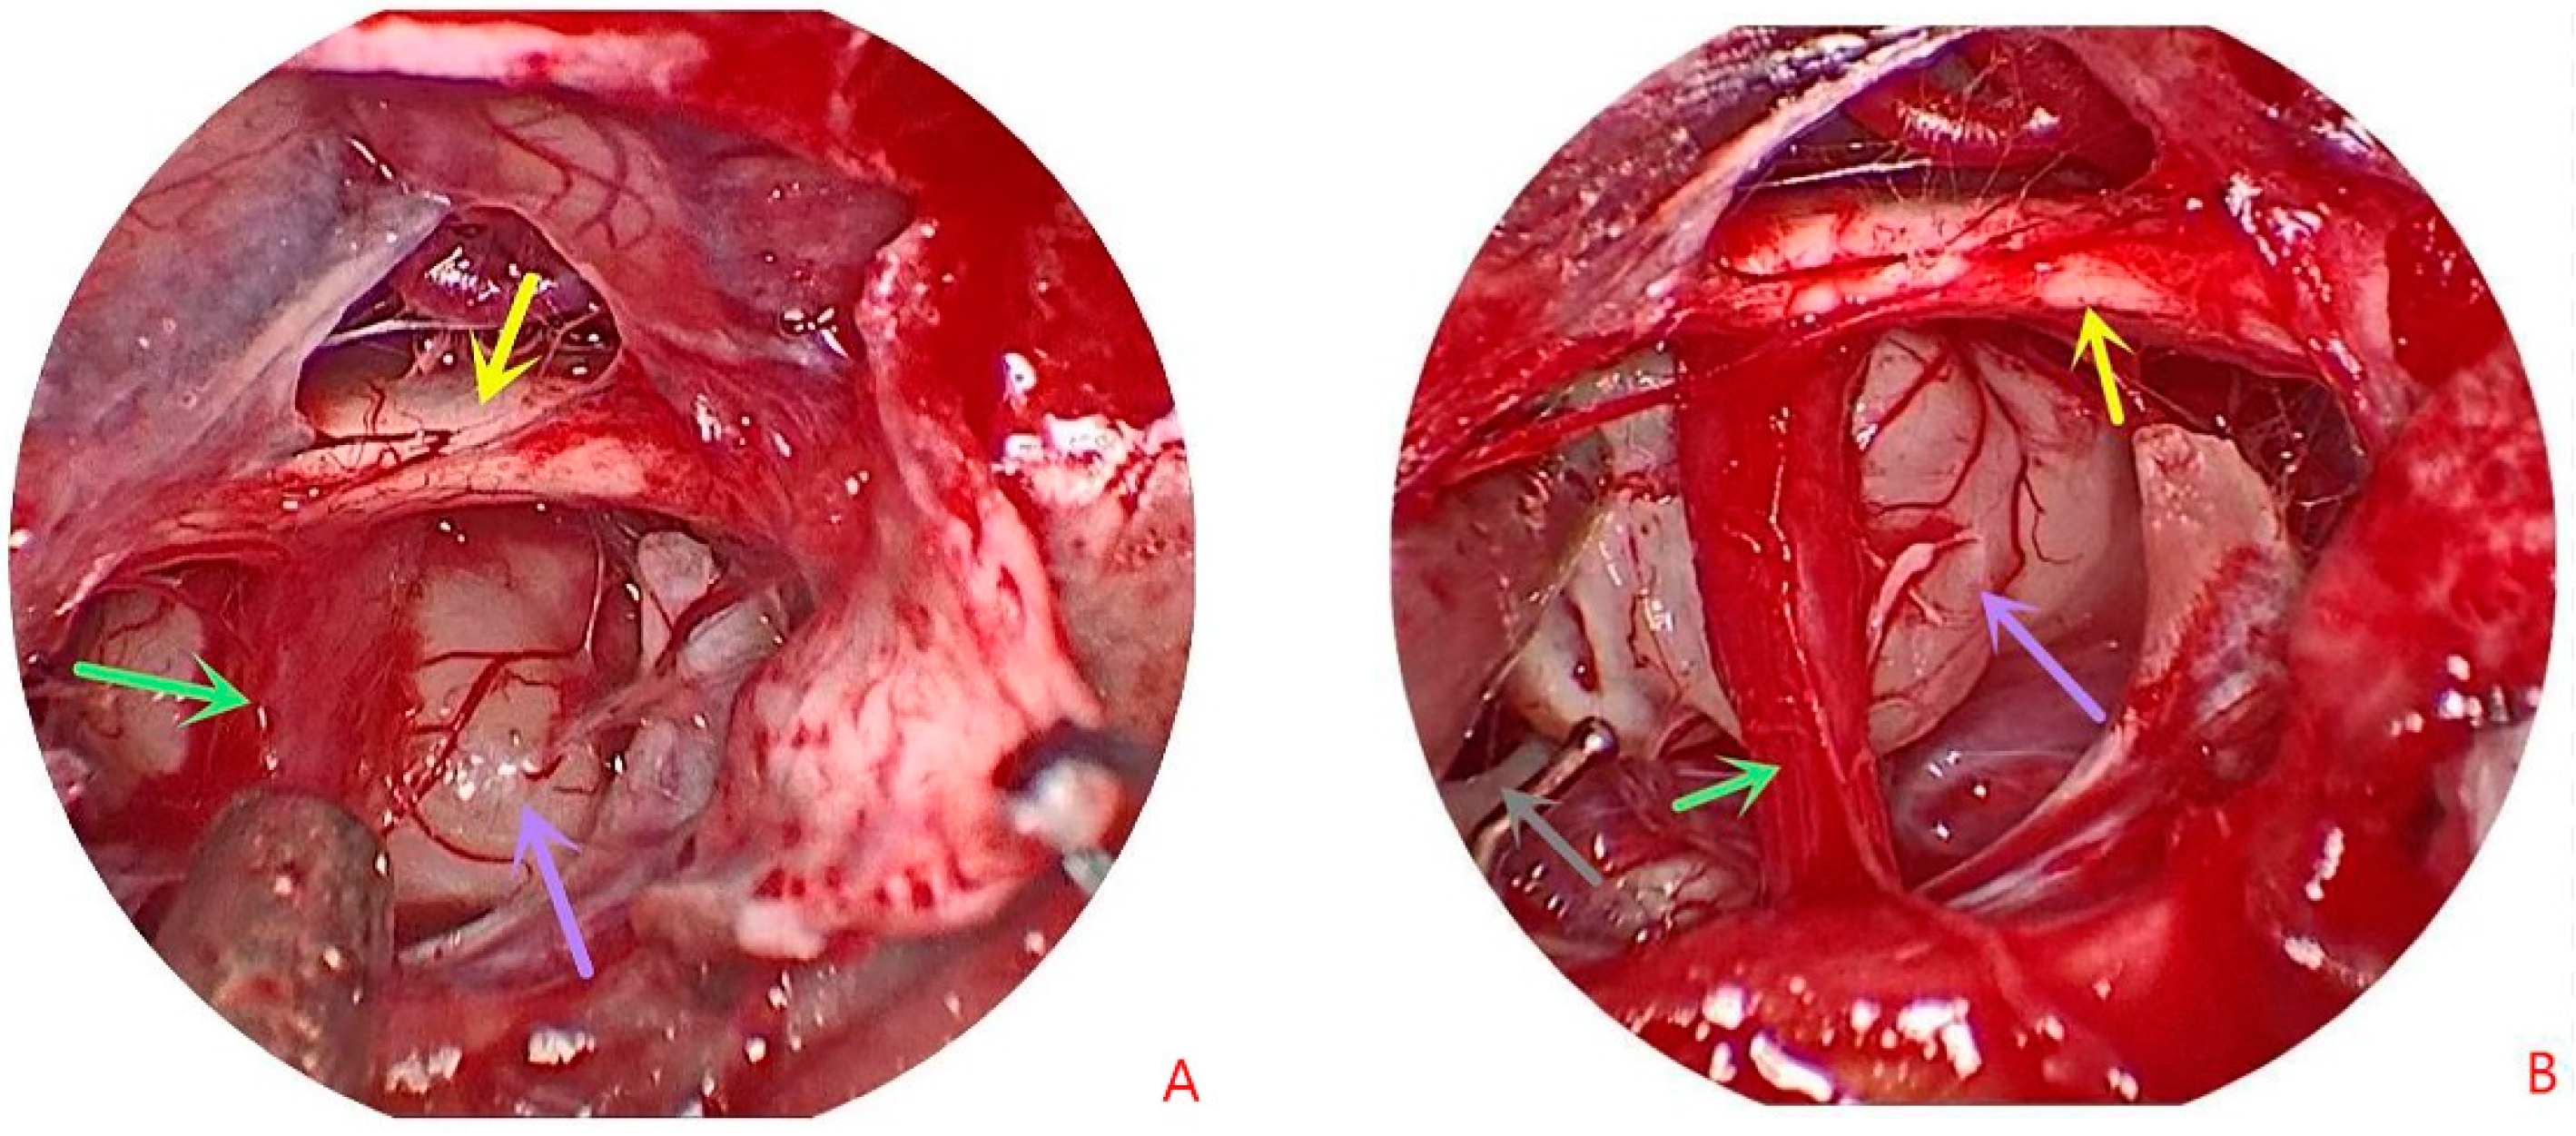

2. Patient Information

3. Operative Note